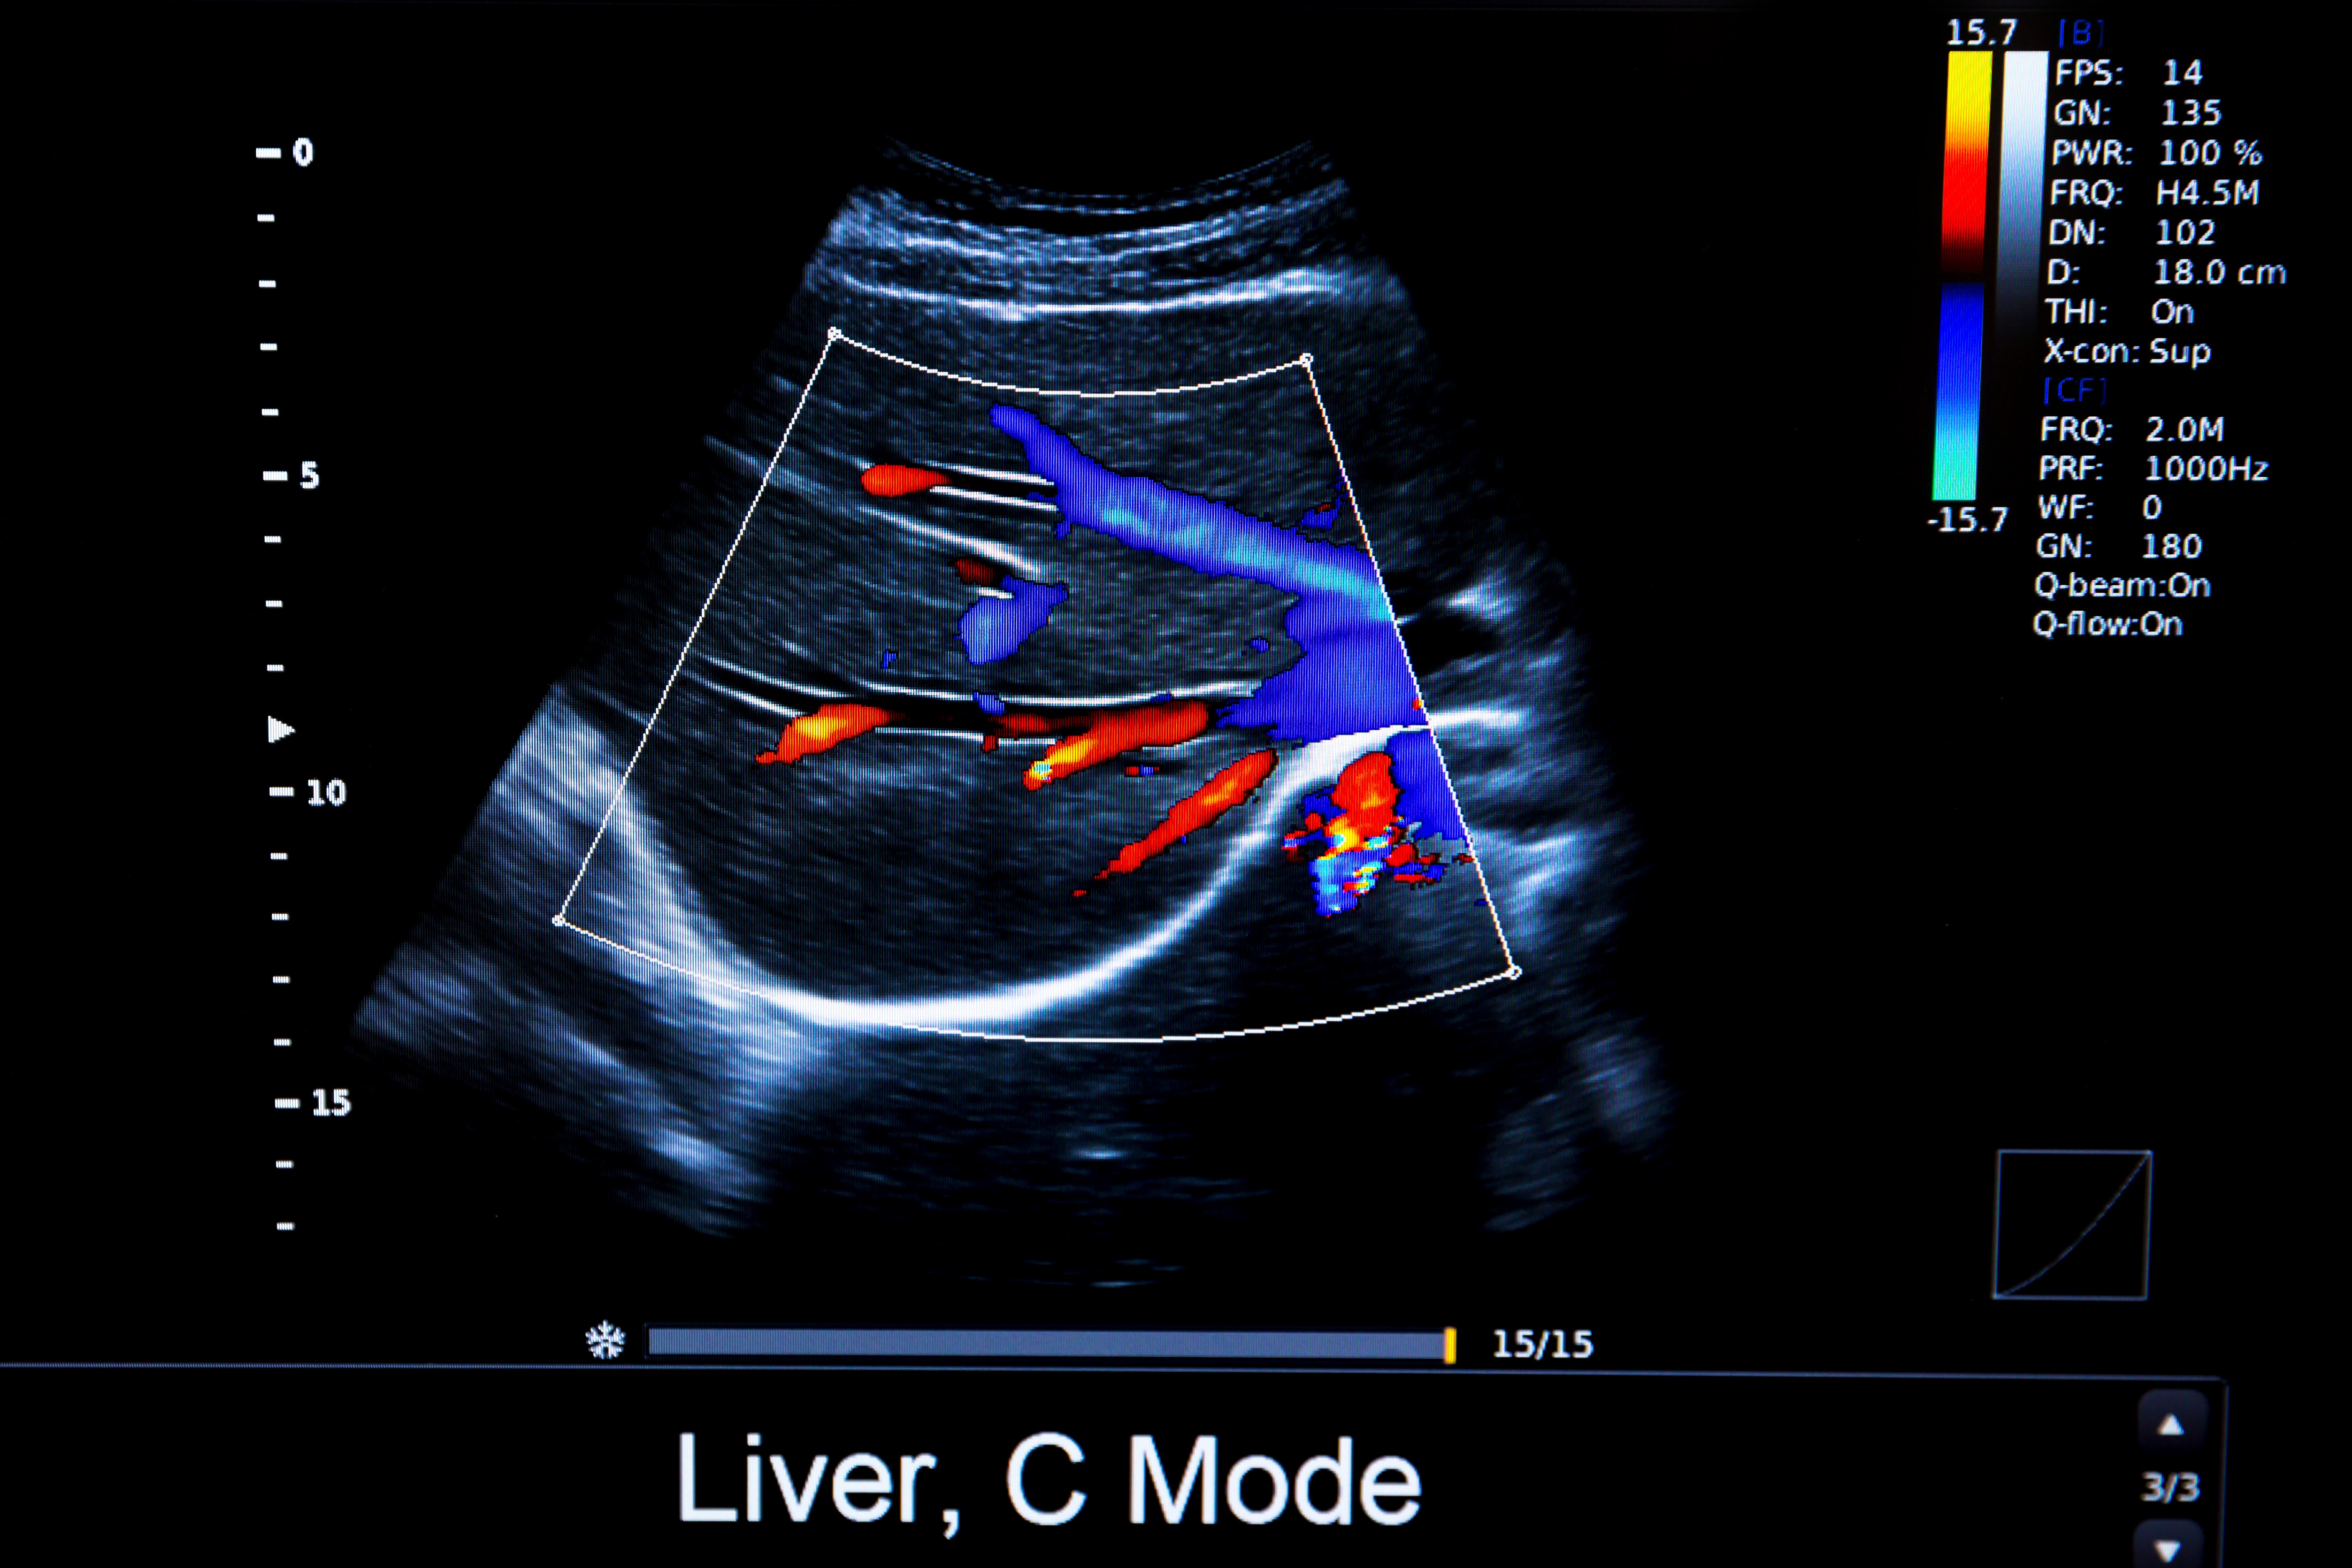

General Ultrasound Studies

Ultrasound can be used to look at all the internal organs of the body with high resolution imaging. It is commonly used as the initial investigation for complaints and symptoms to screen for abnormalities. Ultrasound uses high-frequency sound waves to produce images with no known side effects.